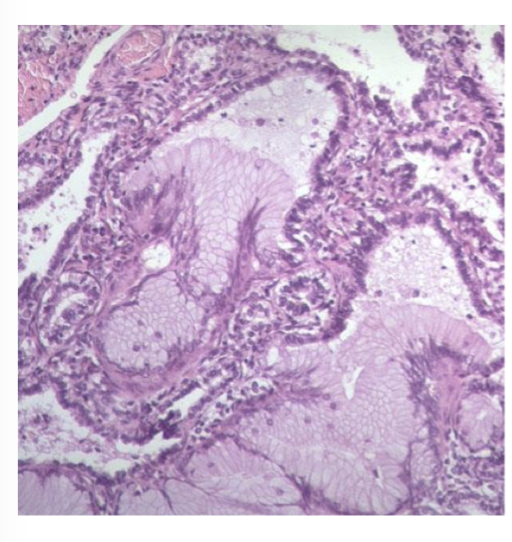

What is the histopathology of congenital cystic adenomatoid malformation (CCAM)? What are the different types?

Alveolar spaces lined by a combination of both respiratory and mucus-secreting epithelium, forming glandular (“adenomatoid”) architecture.

Type 1: large macroscopic cysts

Type 2: small macroscopic cysts

Type 3: microscopic cysts